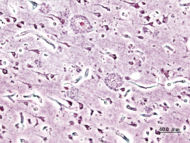

Histopathologic image of senile plaques seen in the cerebral cortex in a patient with Alzheimer disease of presenile onset. Silver impregnation. | |

كما أن المرض يستمر بين ثمانية إلى عشر سنوات، بالرغم من أن بعض المصابين به ، قد يموتون في مرحلة مبكرة ، أو قد يعيشون لفترة 20 عاما. ويمكن للعلاج أن يساعد على إبطاء تطور الزهايمر ، ولكن لا يمكن الشفاء من المرض ، الذي سمي باسم العالم الالماني الذي اكتشفه عام 1906. ويُكتشف المرض بوجود رقع plaques ، وكتل tangles حول وداخل خلايا المخ. وتتكون الرقع من نوع من البروتين الموجود بالمخ ، بينما تتكون الكتل داخل الخلايا العصبية بفعل تشوه يصيب بروتينا آخر، وذلك بحسب ما أفادت وكالة رويترز. وبموت الخلايا العصبية ، يتقلص المخ ، ويفقد مظهره المتجعد.